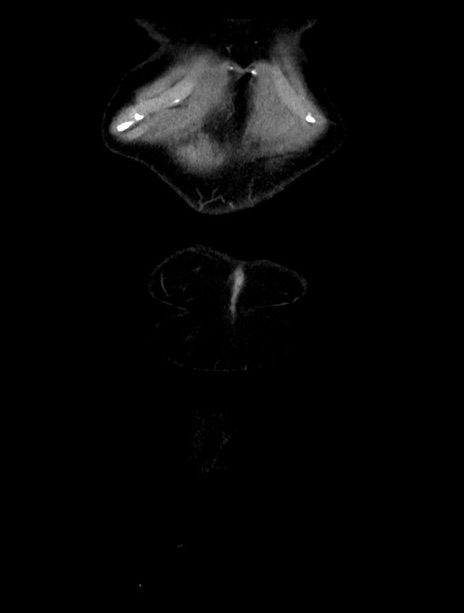

横断像

【症例】70歳代女性

【主訴】下腹部痛・嘔吐

【現病歴】2日前より腹痛あり。昨日嘔吐あり。症状改善しないため来院。

【既往歴】胃GISTに対して胃部分切除後。

【身体所見】BT 37.1℃、BP 128/77mmHg、腹部:平坦・軟、下腹部に圧痛あり。

【データ】WBC 10200、CRP 0.31